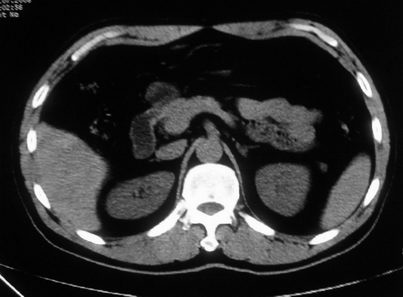

男,体查发现右肝低密度,右肾高密度结节影。高密度ct值92hu,囊肿?

肝右叶囊肿或血管瘤?右肾高密度囊肿。建议增强。

肝右叶圆形低密度灶,考虑囊肿或血管瘤,建议ct增强检查;右肾包膜下高密度圆形灶,考虑:囊肿并出血